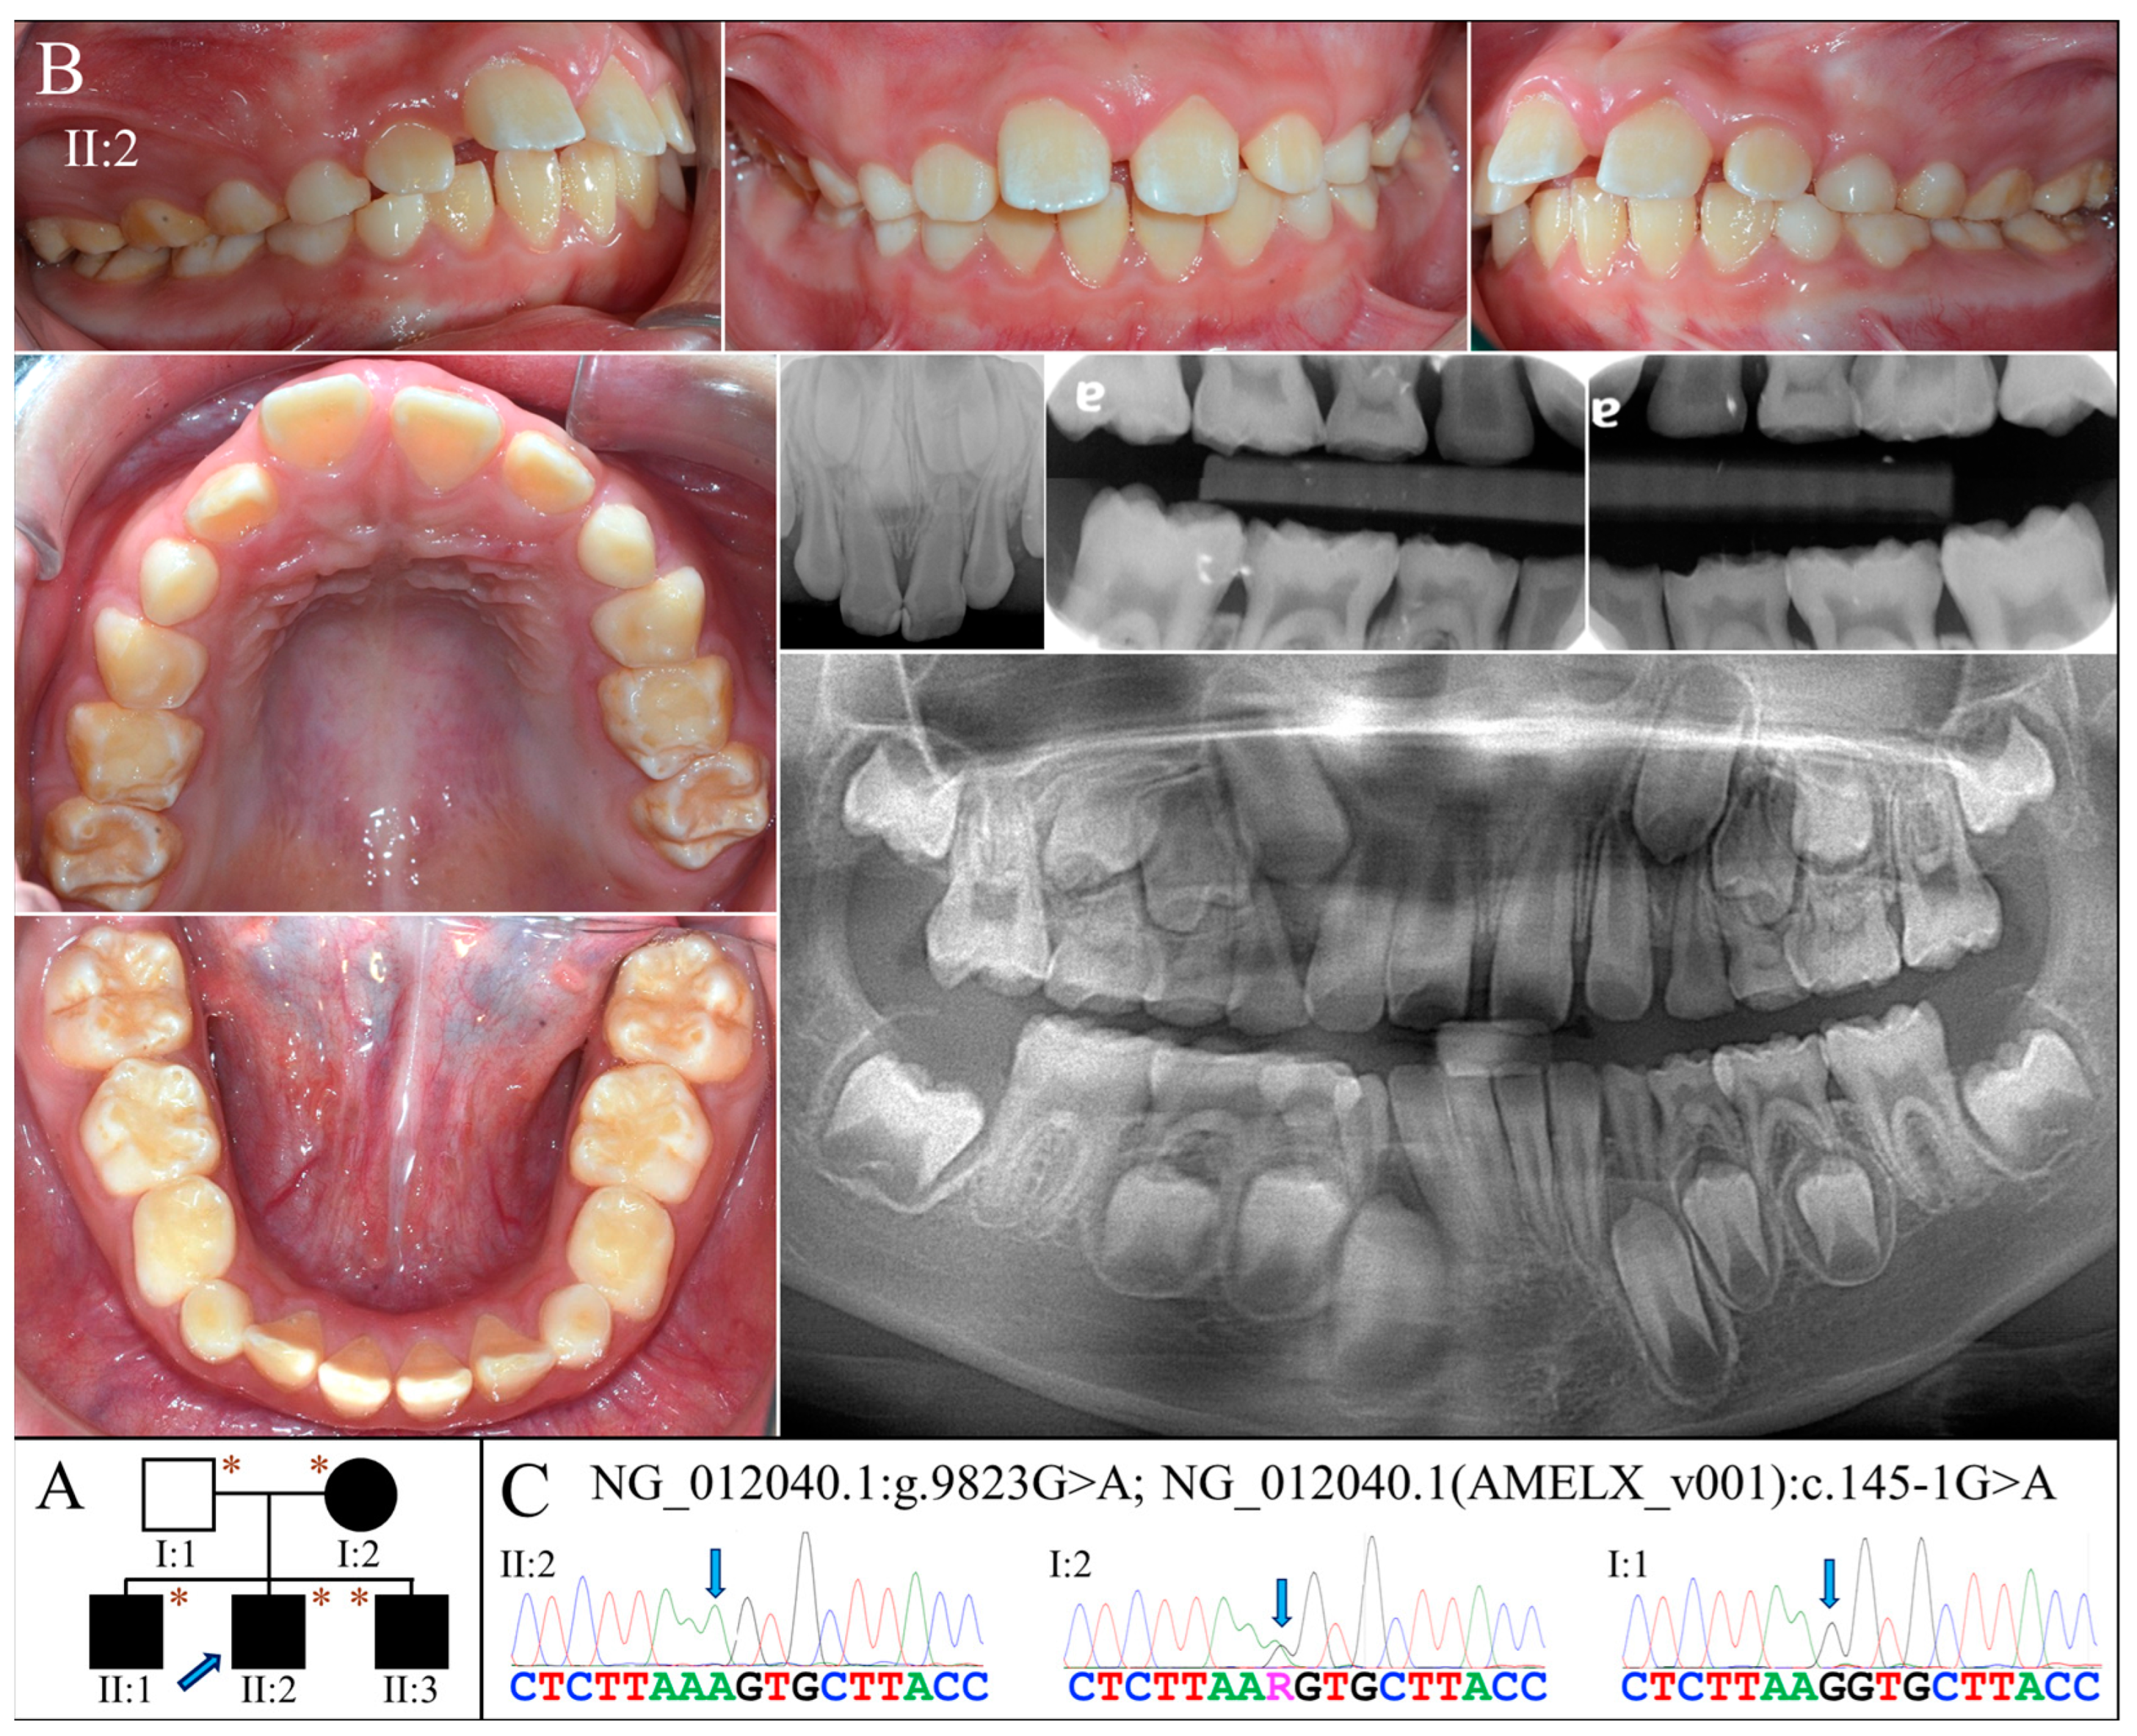

2.4. Family 5 (c.145-1G>A)